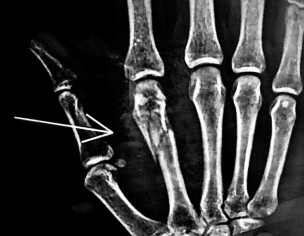

I had an accident and my 2nd Metacarpal Bone of my right hand got fracture. When I tried making fist right after accident, my index finger had malrotation towards middle finger. My doctor saw xrays and did hard plaster. How long will it take to recover estimated? Am I gonna have rotation issue after plaster is removed? Its been 10 days. Should I do something about it or wait for new xray prescribed after 2-3 weeks of plaster/injury.